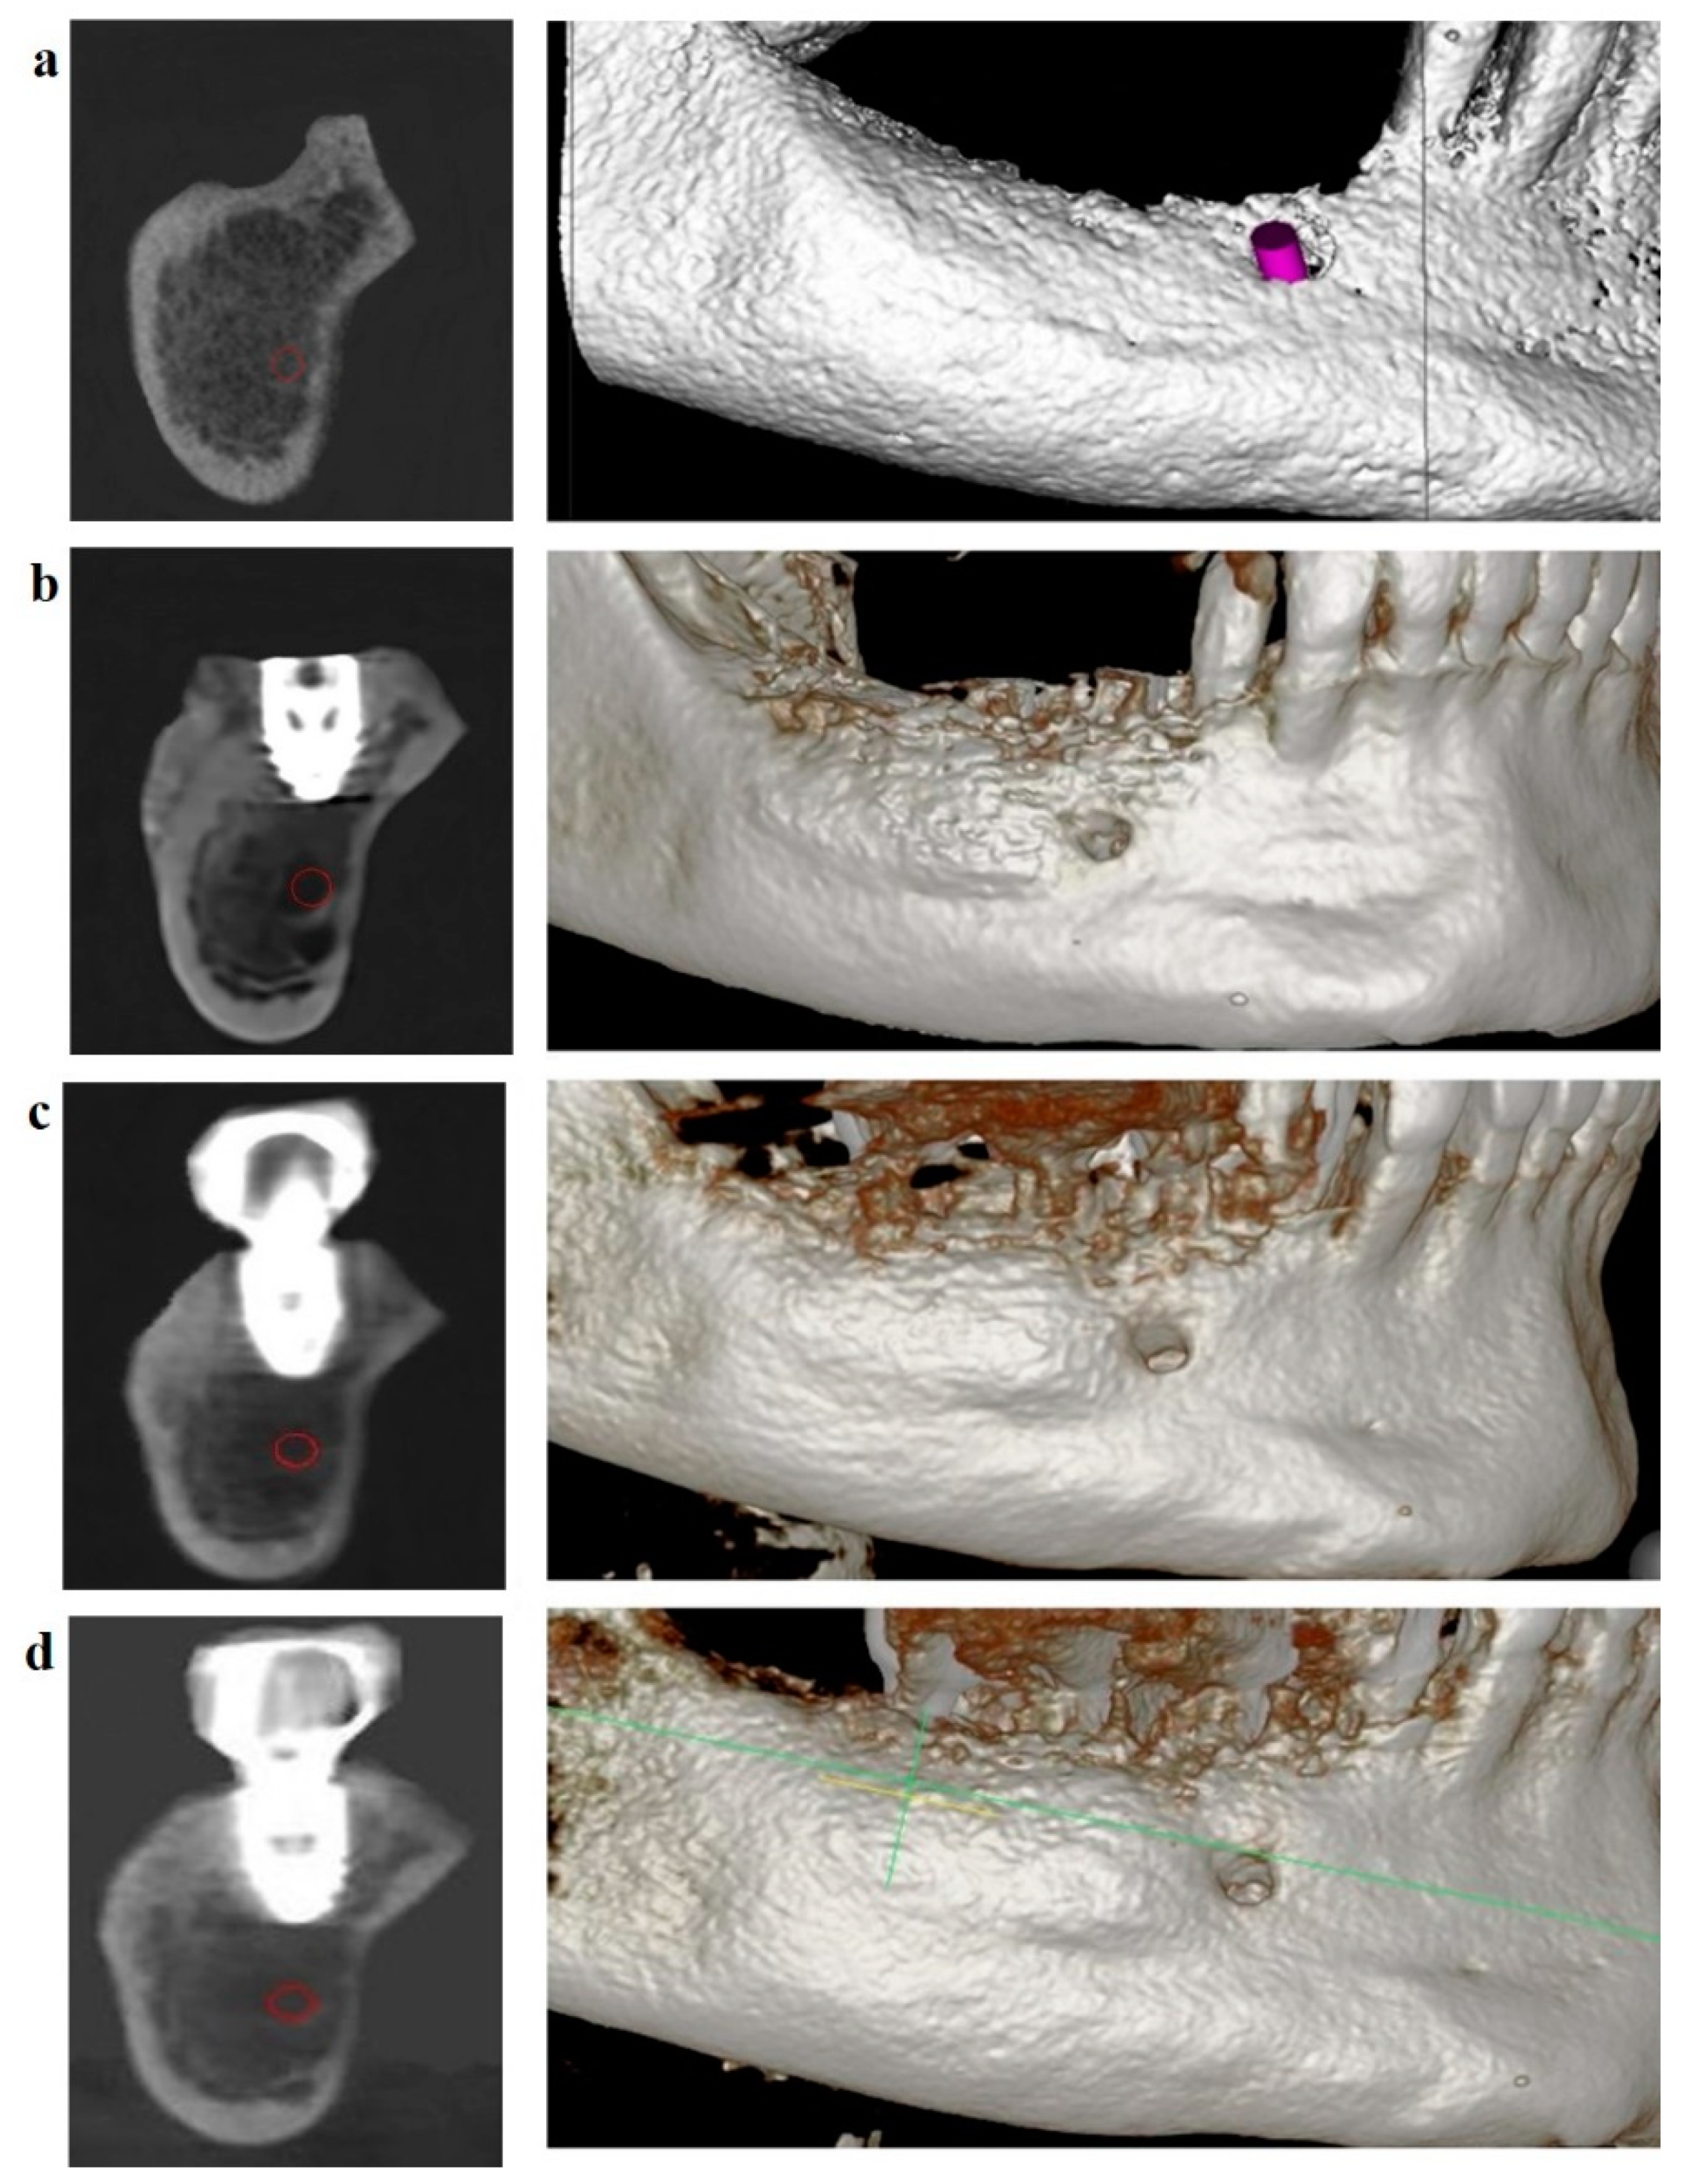

Patients with JBD were treated in three stages: diagnostics and planning for JBD elimination, surgery, and rehabilitation. At the stage of diagnostics and planning, the topography, structure, and volume of JBD were determined, 3D planning of JBD elimination by the GBR method was carried out in the program for 3D modeling of the scaffold [33], and the required graft volume was calculated, and the membrane template was cut (Figure 7).

Dynamic follow-up showed good scaffold stability at four months (Figure 13b), one year and six months after completion of treatment (Figure 13c), and two years and six months after completion of treatment (Figure 13d). The boundaries of the scaffold are located at the level of the dental implant. The OGB fraction was well integrated with the underlying bone.

Figure 13. (a) CBCT of the lower jaw in the projection of the distal implant. JBD before installing the implant; (b) four months after the installation of the implant: the JBD is removed with a sufficient volume of the augmentate, and the boundary between the OGB and the JBD bone is visualized from the vestibular surface; (c) CBCT after one year and six months: successful biotransformation of the augmentate within the planned boundaries of the relief; (d) CBCT after two years and six months.